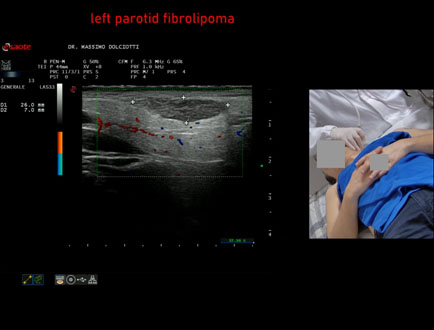

Data inserimento: 09/01/2026

Ecografia del: 22/12/2025

Strumento: Esaote MyLab Eight

Sonda: Lineare Multifrequenza 3-13 MHz

Età Paziente: M 56 anni

Motivazione dell'esame: da alcuni mesi tumefazione parotidea sinistra non dolente.

Commento all'esame: le immagini ed il video documentano formazione iso-ipoecogena, a margini definiti ma irregolari, delle dimensioni di 26 x 7 mm, senza evidenza di vascolarizzazione intra nodulare, da ricondurre, come prima ipotesi, a fibrolipoma, ma meritevole di approfondimento diagnostico.

Conclusioni: fibrolipoma parotideo sinistro (left parotid fibrolipoma).

Presentazione: Dr. Massimo Dolciotti - Ancona

Elaborazione digitale: Andrea Dini - Ancona